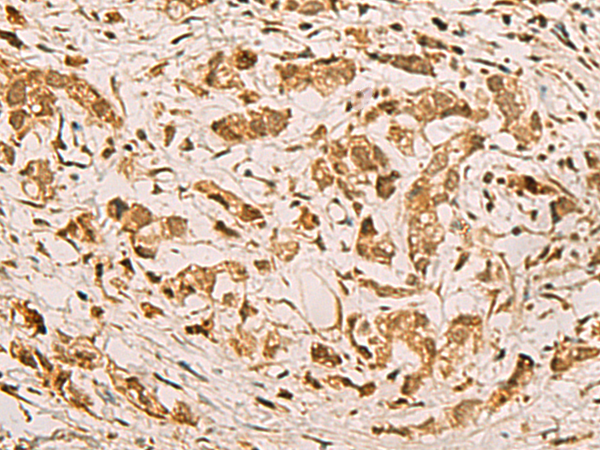

The image is immunohistochemistry of paraffin-embedded Human gastric cancer tissue using (ZMAT4 Antibody) at dilution 1/65.

IHC dilution:1:50-1:200